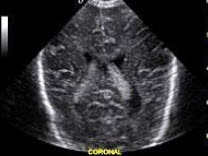

132、单项选择题

图中脑室内高回声区域为()

A.室管膜下出血

B.脉络丛

C.肿瘤

D.脑室出血

E.脑室扩张